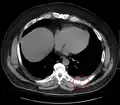

Fracture de côte sur un scanner thoracique Fracture de côte sur un scanner thoracique